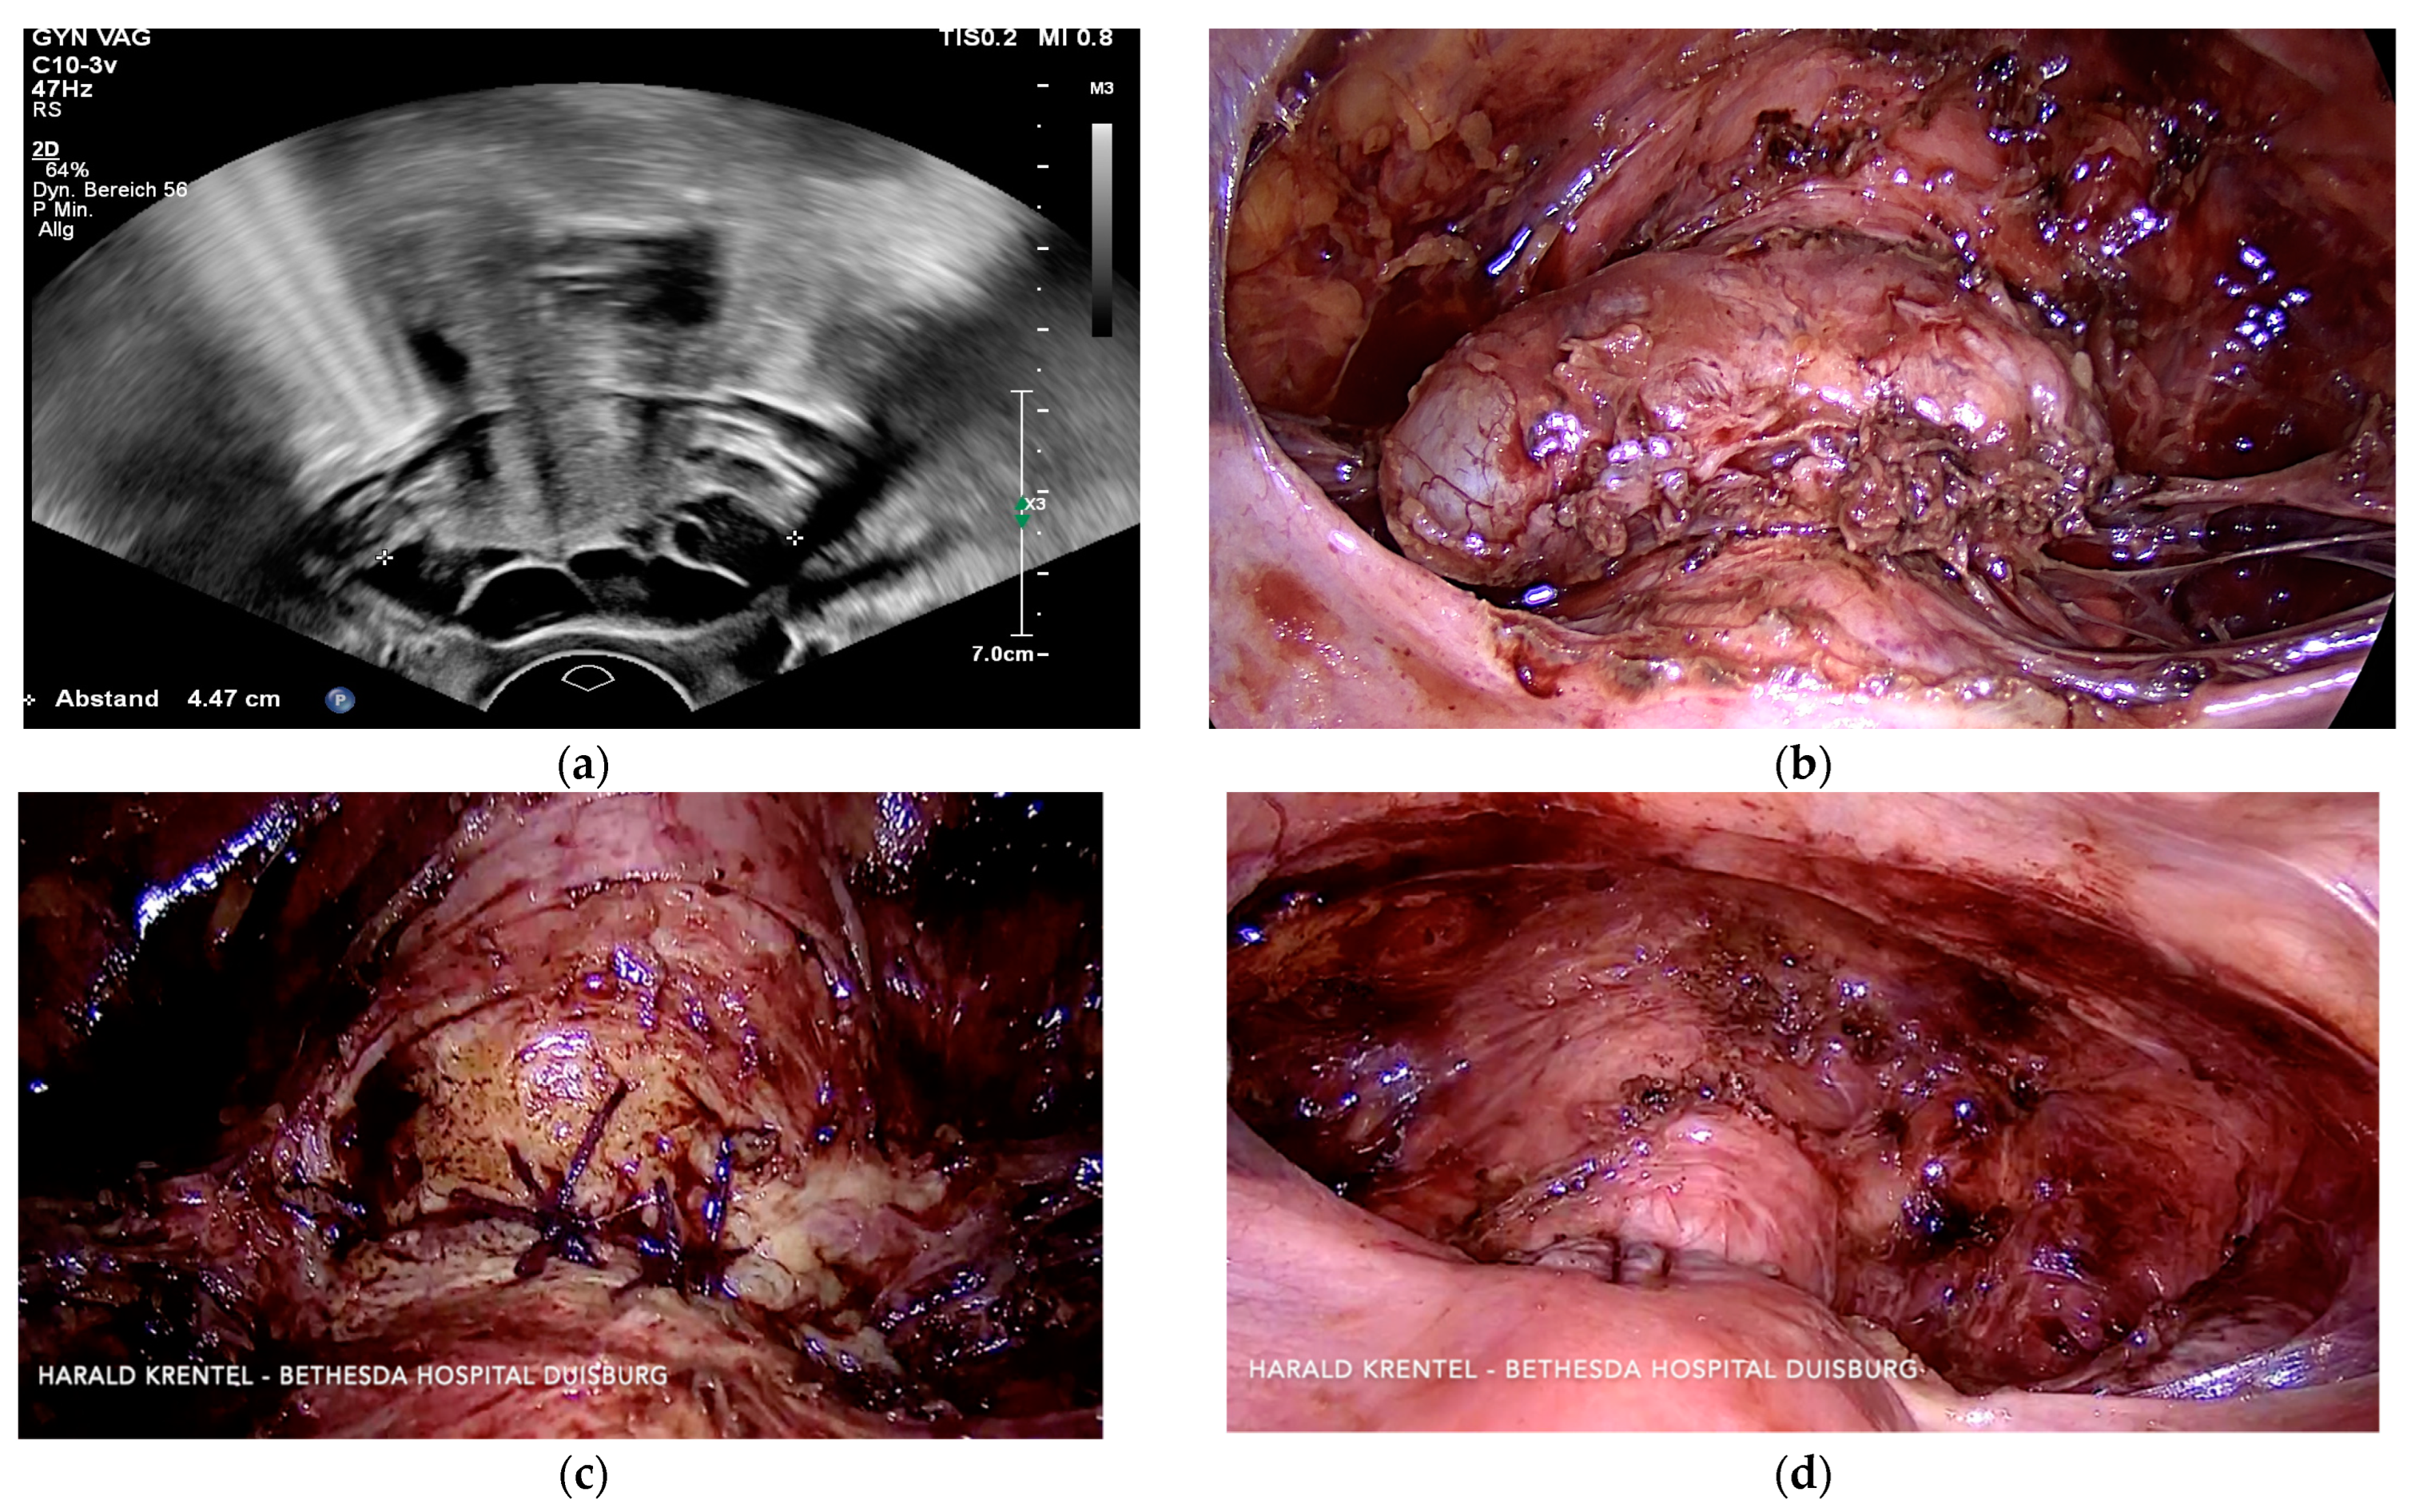

3.3. Case 3—Niche Placentation Failure—Emergency Hysterectomy

3.4. Case 4—Niche Pregnancy—Laparoscopic Subtotal Hysterectomy

3.5. Case 5—Niche Pregnancy—Laparoscopic Resection and Repair

3.6. Case 6—Niche Pregnancy—Combined Hysteroscopic and Laparoscopic Treatment

3.7. Case 7—Symptomatic Niche—Laparoscopic Treatment

3.8. Case 8—Symptomatic Niche—Laparoscopic Treatment

3.9. Case 9 —Symptomatic Isthmozele—Laparoscopic Treatment